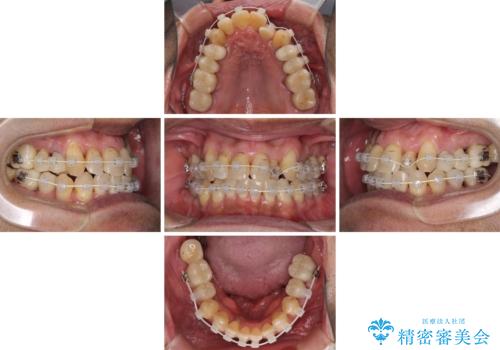

- 前歯がのデコボコや、奥歯に咬んだときに痛みがあるとのことで来院された患者様です。

全体的に問題が多く、全てをしっかりと治療したいとのことでした。

全体的に中等度の歯周病と診断されたため、歯周外科処置やインプラントによる咬合回復から進めて行き、矯正治療による歯列改善を行った後にオールセラミッククラウンにて補綴することとしました。

歯槽骨の再生治療を行ったため、外科処置後の静置期間がながくなり、4年弱の治療期間となりました。